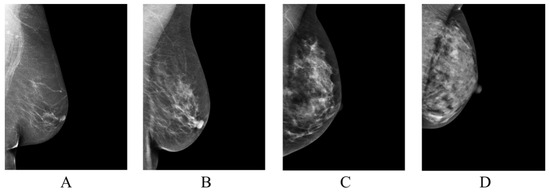

| BI-RADS Category | / |

|---|---|

| Class A | 879/3516 |

| Class B | 3212/12,848 |

| Class C | 928/3712 |

| Class D | 111/444 |

| Total | 5130/20,520 |